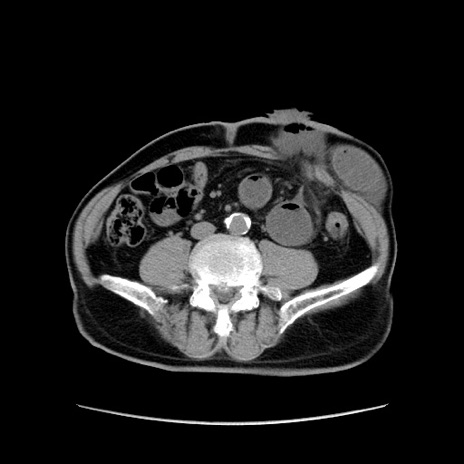

症例24(横断像)

【症例】80歳代男性

【主訴】左側腹部痛、嘔吐

【現病歴】本日早朝より左腹部に痛みあり。昼頃嘔吐認めたため、救急要請。

【既往歴】直腸癌(Mile手術)、胆摘

【身体所見】意識清明、BT 35.9℃、BP 221/93mmHg、SpO2 97%(RA) 、腹部:左ストーマ周囲に限局性の腹部膨隆あり。 膨隆部自発痛・圧痛あり・軟。

【データ】WBC 7700、CRP 0.09